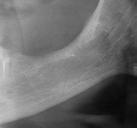

En la ortopantomografía se aprecia una dentición permanente a falta de la erupción de los 2os y 3 os molares, así como una asimetría ósea con rama y cóndilo mandibular izquierdo menos desarrollado (figura 9), causante de la asimetría facial descrita anteriormente.

Figuras 9-11.